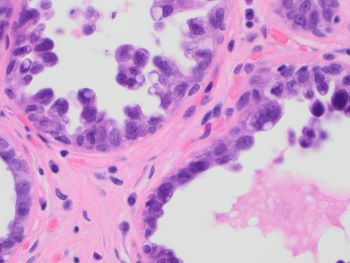

A 51-year-old female presented with extensive microcalcification in the left breast. The morphology of the partial mastectomy is shown in the figures. ER was positive in 50% of the lesional cells.

Correct Answer: C. Cystic hypersecretory intraductal carcinoma